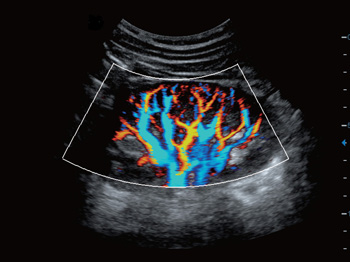

- Функция 3D Color

- Технология SMI для визуализации микроциркуляторного русла и отображения низкоскоростного кровотока в микрососудах

Функция получения трехмерного изображения в режиме цветового допплеровского картирования. Эта функция поможет вам получить качественные трехмерные цветные изображения при проведении исследования. Нужного эффекта удается достичь за счет использования датчи